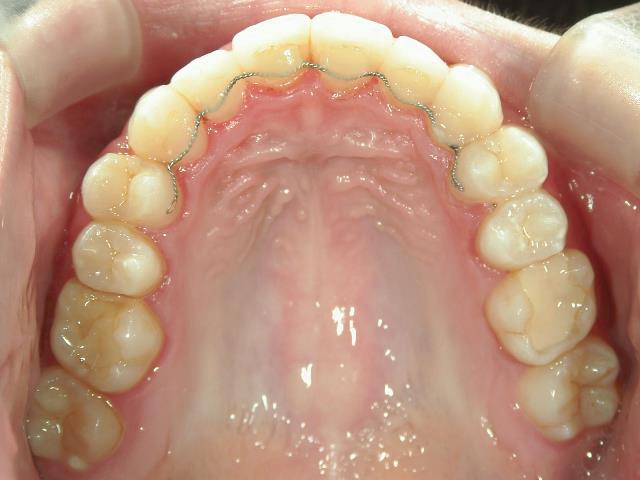

矯正歯科 治療後

矯正歯科 治療後 上顎